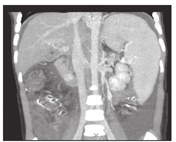

搭桥后血流通畅情况,搭桥前门静脉的平均压力33 cmH2O (26~45 cmH2O),搭桥后门静脉压力下降至18.7 cmH2O(14~24 cmH2O)。肝脏膨胀,脾脏背膜皱缩,游离创面渗血减少。静脉造影显示,分流后肝内门静脉右支及其分支灌注显影,达到肝脏实质边缘。患儿随访6个月至1.5年,超声及增强CT显示所有患儿的搭桥分流血管开放通畅,门静脉海绵变消失,肝体积增大(图3、图4),无消化道出血复发,脾功能亢进症状消失,血小板、白细胞和血红蛋白在正常水平。上消化道造影显示食管静脉曲张明显减轻。